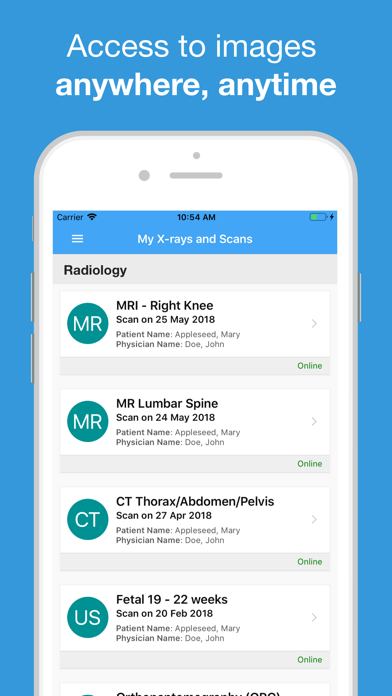

The Infinity Medical Imaging App is used by patients to securely access images and reports

for medical imaging examinations performed at our practice in Chatswood.

Ảnh chụp màn hình của Infinity Medical Imaging App